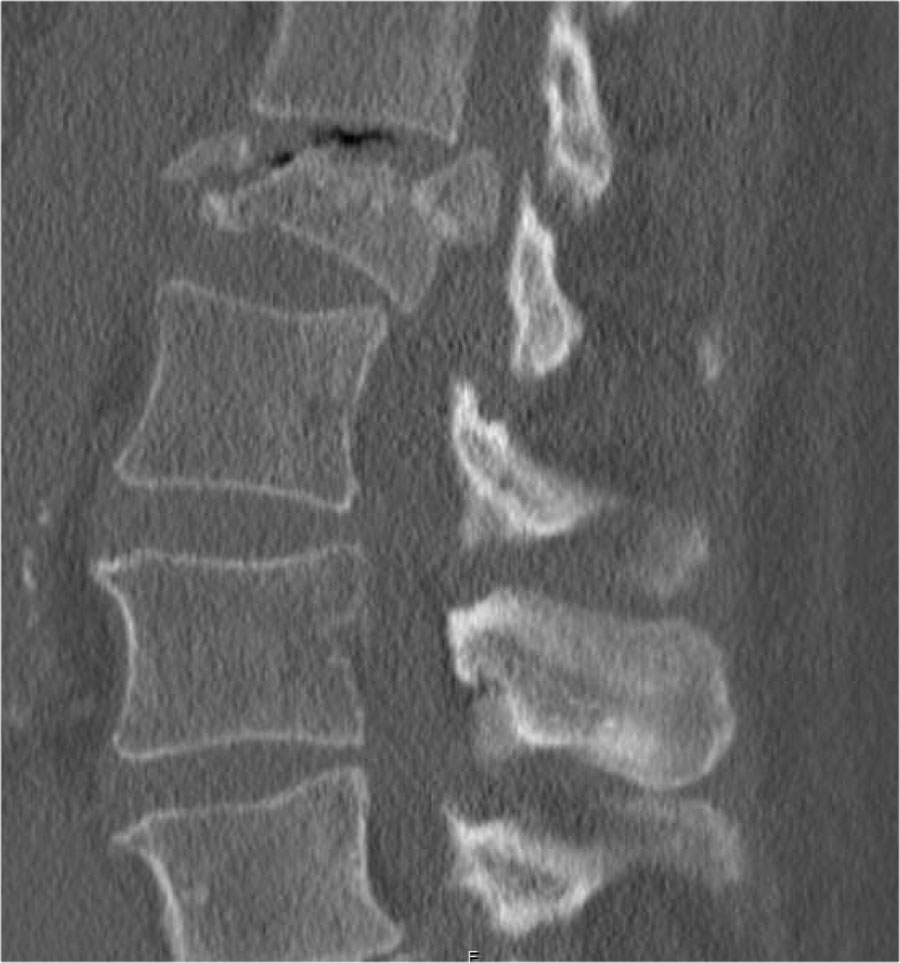

Mảnh xương góc sau trên thân đốt sống bị đẩy lùi ra sau (Retropulsion)

Hiện tượng mảnh xương bị đẩy lùi ra sau là đặc điểm điển hình của gãy vỡ, phân biệt rõ ràng với gãy nén đơn thuần.

Cuộn qua các hình ảnh.

Gãy theo mặt phẳng đứng dọc của thân đốt sống và

cung sau đốt sống

Gãy theo mặt phẳng đứng dọc của thân đốt sống và gãy cung sau theo mặt phẳng đứng dọc gặp lần lượt trong 90% và 85% các trường hợp gãy vỡ.

Dưới đây là bốn ví dụ minh họa.

Trong phân loại Denis, đây sẽ là gãy ba cột — trước/giữa/sau — cho thấy gãy xương rất không vững.

Tuy nhiên, trong phân loại TLICS, đây là gãy vỡ, tức là 2 điểm cho hình thái.

Phương pháp điều trị sẽ phụ thuộc vào tính toàn vẹn của PLC và tình trạng thần kinh.